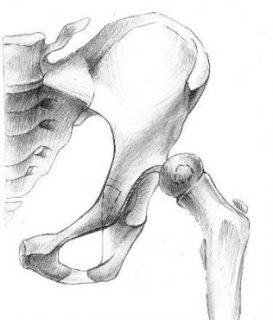

1. Открытое вправление бедра (по типу минимальной артротомии-репозиции)

Применяется у детей первого года жизни при неудаче консервативного лечения.

Раннее установление факта невправимости бедра консервативными способами и выполнение операции на первом году жизни дает возможность уменьшить травматичность хирургического вмешательства. Нет необходимости вмешиваться на костях таза и бедра.

Рентгенограммы больной Т., 10 месяцев. Диагноз: врожденный вывих бедра справа.